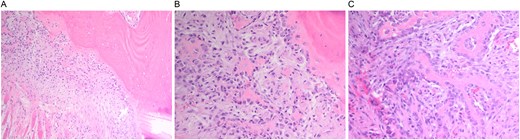

A multidisciplinary discussion involving orthopedic, maternal-fetal medicine, and head and neck teams determined the treatment plan. Further biopsy confirmed the brown tumor diagnosis, showing multinucleated giant cells, mononuclear stromal cells, bone resorption, and osteoclast clustering (Fig. 2A–C). Six days after the presentation, she was deemed suitable for parathyroidectomy. Although at high risk for pathologic fracture, she declined prophylactic fixation during pregnancy. Two days after a successful parathyroidectomy, she underwent an uncomplicated Cesarean section. As her calcium levels normalized, plans for femoral fixation were made post-childbirth. One week postpartum, the patient fell, resulting in a pathologic fracture of the left distal femur and ipsilateral iliac wing fracture (Fig. 3A and B).

(A and B) Pathologic fracture involving the left distal femur and left iliac bone.